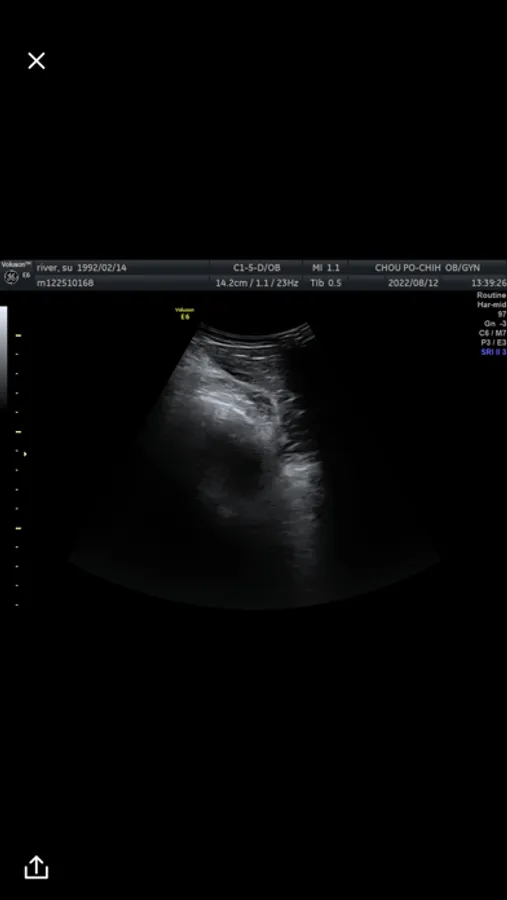

Chou Po-Chih Obstetrics and Gynecology Clinic

苗栗周博治婦產科超音波app,提供最即時的超音波影像

周博治婦產科 Screenshots